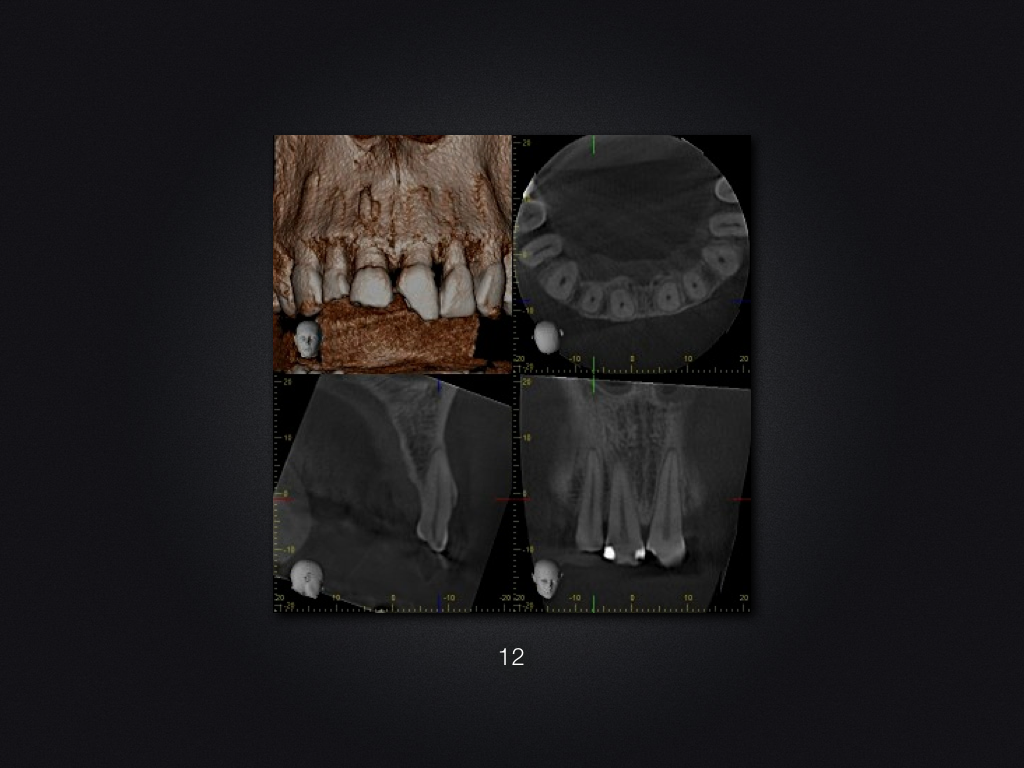

11 21 D.004

Trauma-„Zweitversorgung“